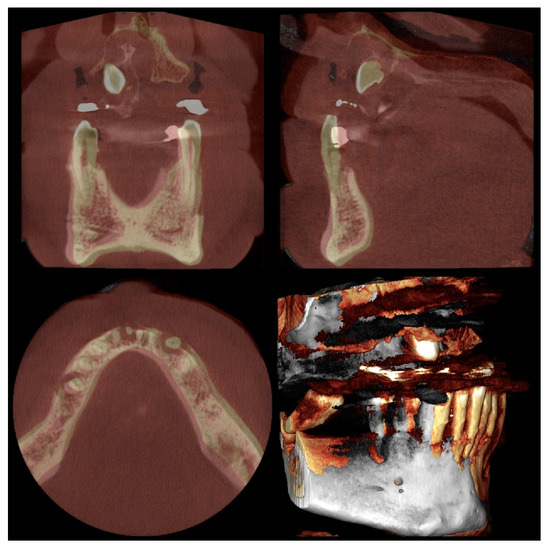

| Patient/Age | Surgeon | Tooth | MM‘s Power Set | MM Insert | Instrument’s Insertion Depth | Extraction Time | T0 | T3 |

|---|---|---|---|---|---|---|---|---|

| S.M.—66 | D.B. | 16 | 2–3 | EXTR 3 | 5 mm | 4 min | 12.8 | 11 |

| M.F.—70 | D.B. | 12 | 2 | EXTR 3F | 4 mm | 3 min | 7.97 | 6.72 |

| 11 | 2 | EXTR 3F | 4 mm | 2 min | 7.88 | 6.38 | ||

| 21 | 2 | EXTR 3F | 4 mm | 2 min | 6.77 | 5.02 | ||

| 22 | 2 | EXTR 3F | 4 mm | 4 min | 7.83 | 6.58 | ||

| 32 | 3 | EXTR 3F | 4 mm | 5 min | 7.78 | 6.03 | ||

| G.F.—59 | D.B. | 13 | 2 | EXTR 2F | 5 mm | 5 min | 8.2 | 6.2 |

| 12 | 2 | EXTR 2F | 3 mm | 5 min | 6.5 | 4 | ||

| 11 | 2 | EXTR 2F | 3 mm | 2 min | 6.4 | 5.7 | ||

| 21 | 2 | EXTR 2F | 4 mm | 3 min | 8.2 | 7 | ||

| 22 | 2 | EXTR 2F | 5 mm | 2 min | 7.2 | 6 | ||

| 23 | 2 | EXTR 2F | 5 mm | 5 min | 8.7 | 6 | ||

| 17 | 3 | EXTR 2F | 5 mm | 5 min | 10.4 | 8.6 | ||

| M.M.—62 | D.B. | 25 | 3 | EXTR 2F | 4 mm | 6 min | 8.1 | 7 |

| 22 | 3 | EXTR 2F | 4 mm | 7 min | 7.25 | 6 | ||

| 23 | 2 | EXTR 2F | 5 mm | 5 min | 6.3 | 4.6 | ||

| 21 | 2 | EXTR 3F | 4 mm | 2 min | 8 | 6.5 | ||

| 11 | 2 | EXTR 3F | 4 mm | 2 min | 8.4 | 7 | ||

| 12 | 2 | EXTR 3F | 4 mm | 2 min | 7.5 | 6.5 | ||

| 27 | 3 | EXTR 2F | 5 mm | 5 min | 11.4 | 10 | ||

| C.M.—73 | D.B. | 21 | 3 | EXTR 3F | 5 mm | 3 min | 5.6 | 4.2 |

| 22 | 2 | EXTR 3F | 5 mm | 3 min | 5.97 | 4.12 | ||

| F.M.—65 | D.B. | 34 | 1 | EXTR 3F | 6 mm | 2 min | 7.01 | 5.26 |

| J.C.—72 | J.C. | 43 | 2 | EXTR 4F | 4 mm | 4 min | 6.82 | 5.48 |

| J.C.—72 | J.C. | 42 | 2 | EXTR 2F | 4 mm | 5 min | 6.28 | 4.89 |

| J.C.—72 | J.C. | 41 | 2 | EXTR 2F | 4 mm | 2 min | 5.69 | 3.92 |

| J.C.—72 | J.C. | 31 | 2 | EXTR 2F | 4 mm | 3 min | 5.56 | 3.8 |

| J.C.—72 | J.C. | 32 | 2 | EXTR 2F | 4 mm | 2 min | 6.42 | 4.75 |

| L.M.—38 | J.C. | 24 | 1 | EXTR 3F | 5 mm | 2 min | 8.92 | 7.46 |